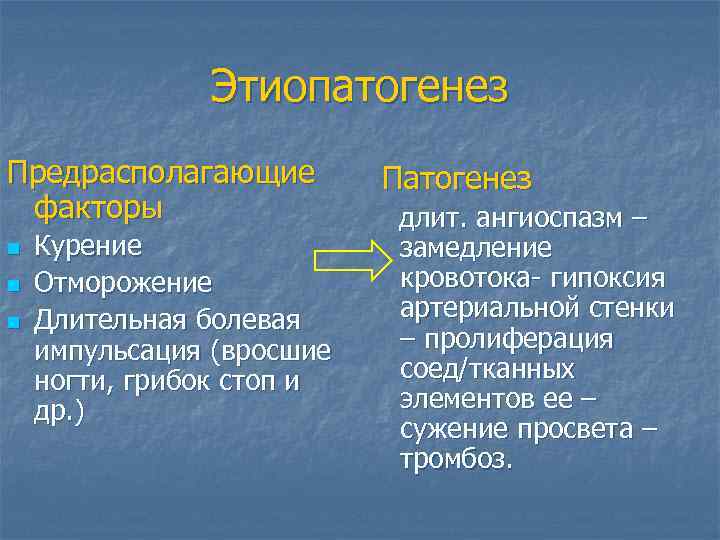

Этиопатогенез Предрасполагающие факторы n n n Курение Отморожение Длительная болевая импульсация (вросшие ногти, грибок стоп и др. ) Патогенез длит. ангиоспазм – замедление кровотока- гипоксия артериальной стенки – пролиферация соед/тканных элементов ее – сужение просвета – тромбоз.